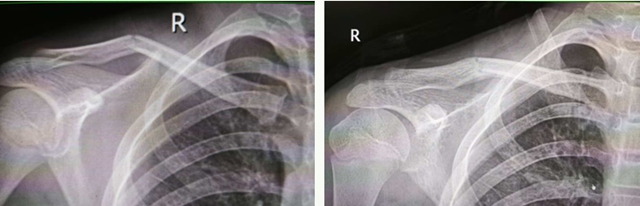

左:复位前 右:复位后

小林的锁骨骨折最为严重,为粉碎性,若行开放手术,不仅手术切口大,出血多,钢板内固定后还可能影响骨骼后续生长。传统中医手法正骨具有不开刀、不出血、不留疤、费用低等特点。医生运用“推端提按、抱迫靠拢”等正骨手法,蓄力指尖,擒拿扶正,将分散的骨折碎片精准拼接、复位;再用杉树皮小夹板固定,既牢牢锁住骨折端避免再次移位,又不压迫局部皮肤导致皮肤溃疡;同时辅以医院自制的消肿止痛中药外敷,辅以活血化瘀内服方剂,促进骨痂生长和创伤修复。

其中,15岁的小林伤势最为严重,骨折为粉碎性,多个骨碎片游离,骨折断端移位明显,并有戳破皮肤趋势。

另外2名少年虽然也同时出现锁骨骨折,只是病情相对较轻,骨折端移位相对不大。